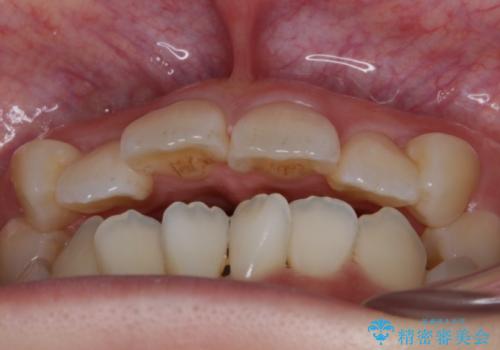

- 前歯のガタつき・噛み合わせの不調を主訴にご来院されました。

患者様のお仕事柄、目立たない装置で矯正したいとのご要望があり、今回はインビザラインを用いて抜歯矯正を行うこととなりました。

本来、抜歯によって得られる大きなスペースのコントロールはワイヤー装置の方が得意とされていますが、こちらの患者様のように犬歯が大きく手前に傾斜していて奥歯の噛み合わせにそれほど問題がないケースではマウスピース装置でも十分にコントロールできることが予測されます。

歯のガタつきの度合いが強い場合や、上下で大きく噛み合わせがズレている時などに、その改善のための大きなスペースを作る代表的手段が「抜歯」です。

一般的には第一小臼歯(犬歯の一つ隣の歯)を抜くことが多く、前歯のガタつきを改善したり口元を引っ込める場合に利用されます。